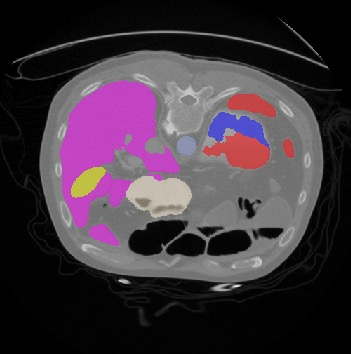

Transformers, the default model of choices in natural language processing, have drawn scant attention from the medical imaging community. Given the ability to exploit long-term dependencies, transformers are promising to help atypical convolutional neural networks (convnets) to overcome its inherent shortcomings of spatial inductive bias. However, most of recently proposed transformer-based segmentation approaches simply treated transformers as assisted modules to help encode global context into convolutional representations without investigating how to optimally combine self-attention (i.e., the core of transformers) with convolution. To address this issue, in this paper, we introduce nnFormer (i.e., Not-aNother transFormer), a powerful segmentation model with an interleaved architecture based on empirical combination of self-attention and convolution. In practice, nnFormer learns volumetric representations from 3D local volumes. Compared to the naive voxel-level self-attention implementation, such volume-based operations help to reduce the computational complexity by approximate 98% and 99.5% on Synapse and ACDC datasets, respectively. In comparison to prior-art network configurations, nnFormer achieves tremendous improvements over previous transformer-based methods on two commonly used datasets Synapse and ACDC. For instance, nnFormer outperforms Swin-UNet by over 7 percents on Synapse. Even when compared to nnUNet, currently the best performing fully-convolutional medical segmentation network, nnFormer still provides slightly better performance on Synapse and ACDC.